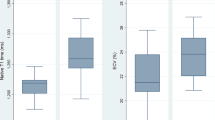

Post-race RVEF was reduced and RV cardiac volumes were increased, while no change in LV function and cardiac volumes was observed on CMR (Fig. 2). On TTE, post-race reductions of strain were more pronounced in the RV than in the LV, with borderline reduced LV global longitudinal strain (GLS). Atrial volumes and left atrial function did not change, while right atrial—reservoir and -conduit strain were significantly reduced following high-intensity cycling.

Changes in right ventricular EF (a), EDVi (b) and ESVi (c) between pre- and post-exercise** in 17 cyclists. Data are presented as mean and as the individual changes in right ventricular EF, EDVi and ESVi between pre- and post-exercise. EF ejection fraction, EDVi end-diastolic volume index, ESVi end-systolic volume index, ml millimeters